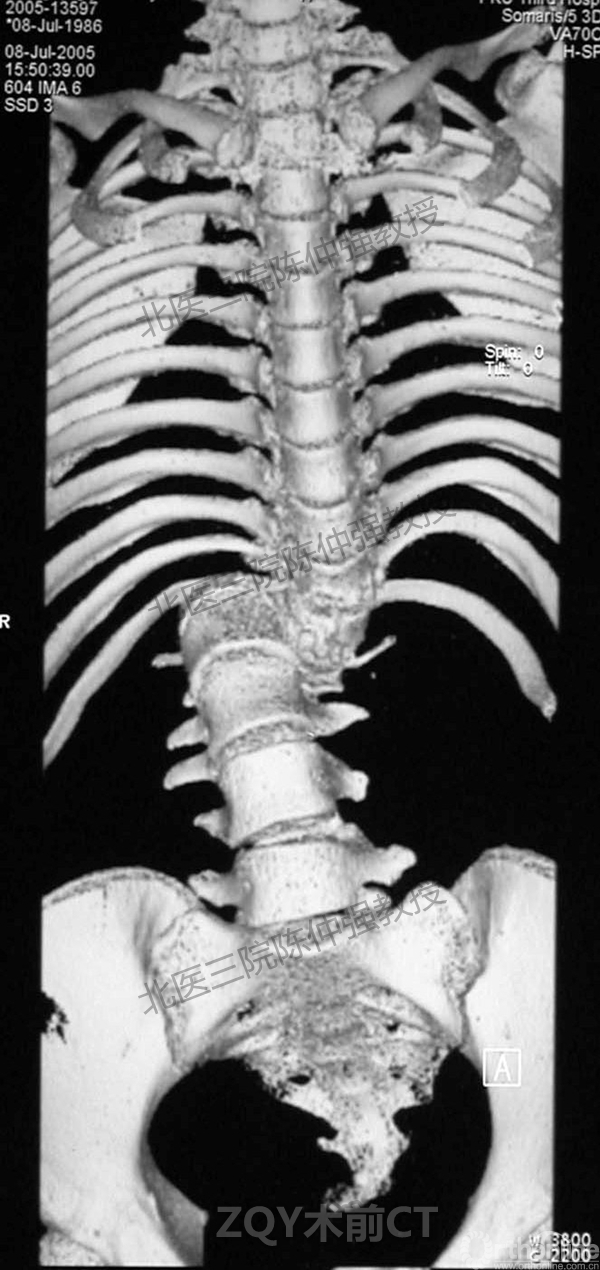

2005年,陈仲强教授在AOSpine年会上分享了一例胸腰椎陈旧结核性侧后凸畸形病例。资料如下:

ZQY术前

患者女性17岁,胸腰椎陈旧结核性侧后凸畸形,局部呈“麻花状”扭转,无神经功能受损表现。2005年,陈仲强教授带领团队实施后路+侧前方联合入路脊柱节段切除、双轴旋转矫形术。术后患者外观显著改善,神经功能正常。术后随访证实患者截骨矫形节段骨性融合良好,矫形效果持续良好。